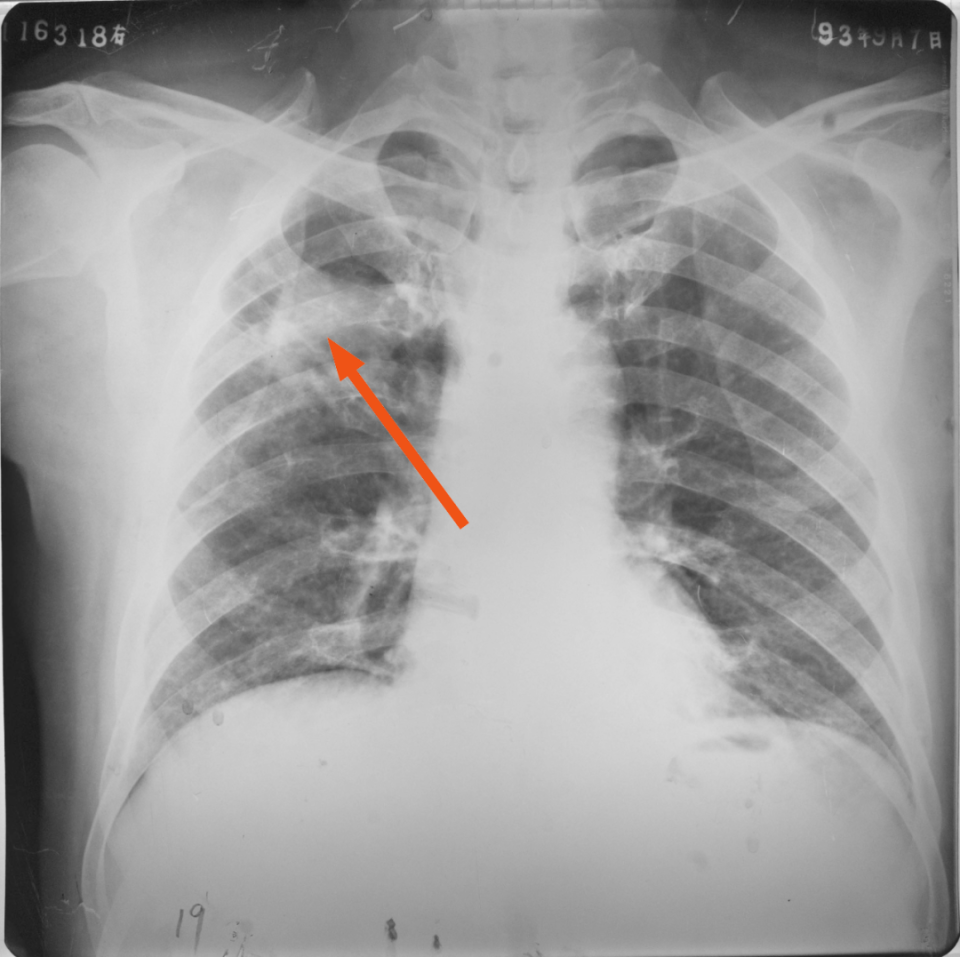

右上、下肺支原体肺炎

图片

胸部正位片示:右上、下肺野肺纹理增粗,可见斑片状阴影,密度较淡,局部呈扇形自肺门部发出(箭头所指)